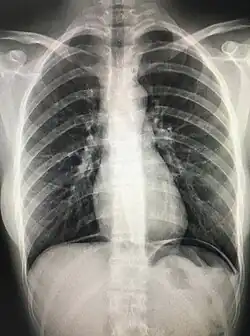

The cupola sign is seen on a supine chest or abdominal radiograph in the presence of pneumoperitoneum.

It refers to air that rises within the abdominal cavity of the supine patient to accumulate underneath the central tendon of the diaphragm in the midline. It is seen as lucency overlying the lower thoracic vertebral bodies. The superior border is well defined, but the inferior margin is not.